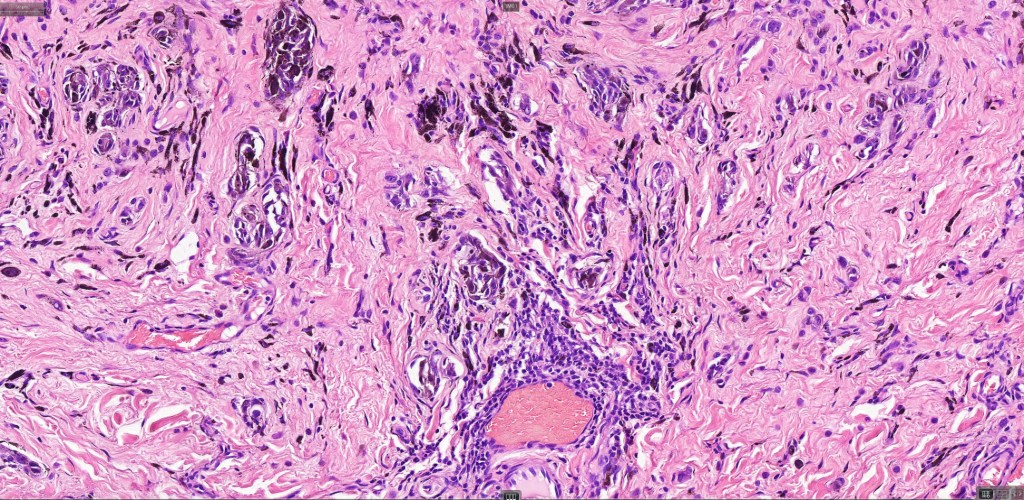

This is uncommon and presents clinically with a history of recent change in color of a common or less often congenital nevus causing concern for melanoma by the clinician. Some, but not all are probably deep penetrating and combined nevus variants. Others may represent follicular type-A cell nests. It is characterized by the presence of deep nest(s) of type -A nevus cells surrounded by & with overlying type-B nevus cells.